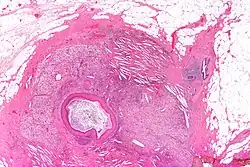

Micrograph of squamous metaplasia of lactiferous ducts. H&E stain.

Squamous metaplasia of lactiferous ducts - abbreviated SMOLD is a change where the normal double layer cuboid epithelium of the lactiferous ducts is replaced by squamous keratinizing cell layers. The resulting epithelium is very similar to normal skin, hence some authors speak of epidermalization. SMOLD is rare in premenopausal women (possibly 0.1-3%) but more frequent (possibly up to 25%) in postmenopausal women where it does not cause any problems at all.